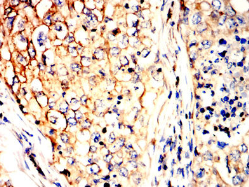

P4HB Mouse Monoclonal antibody[3F12C]

IHC    1/200 - 1/1000